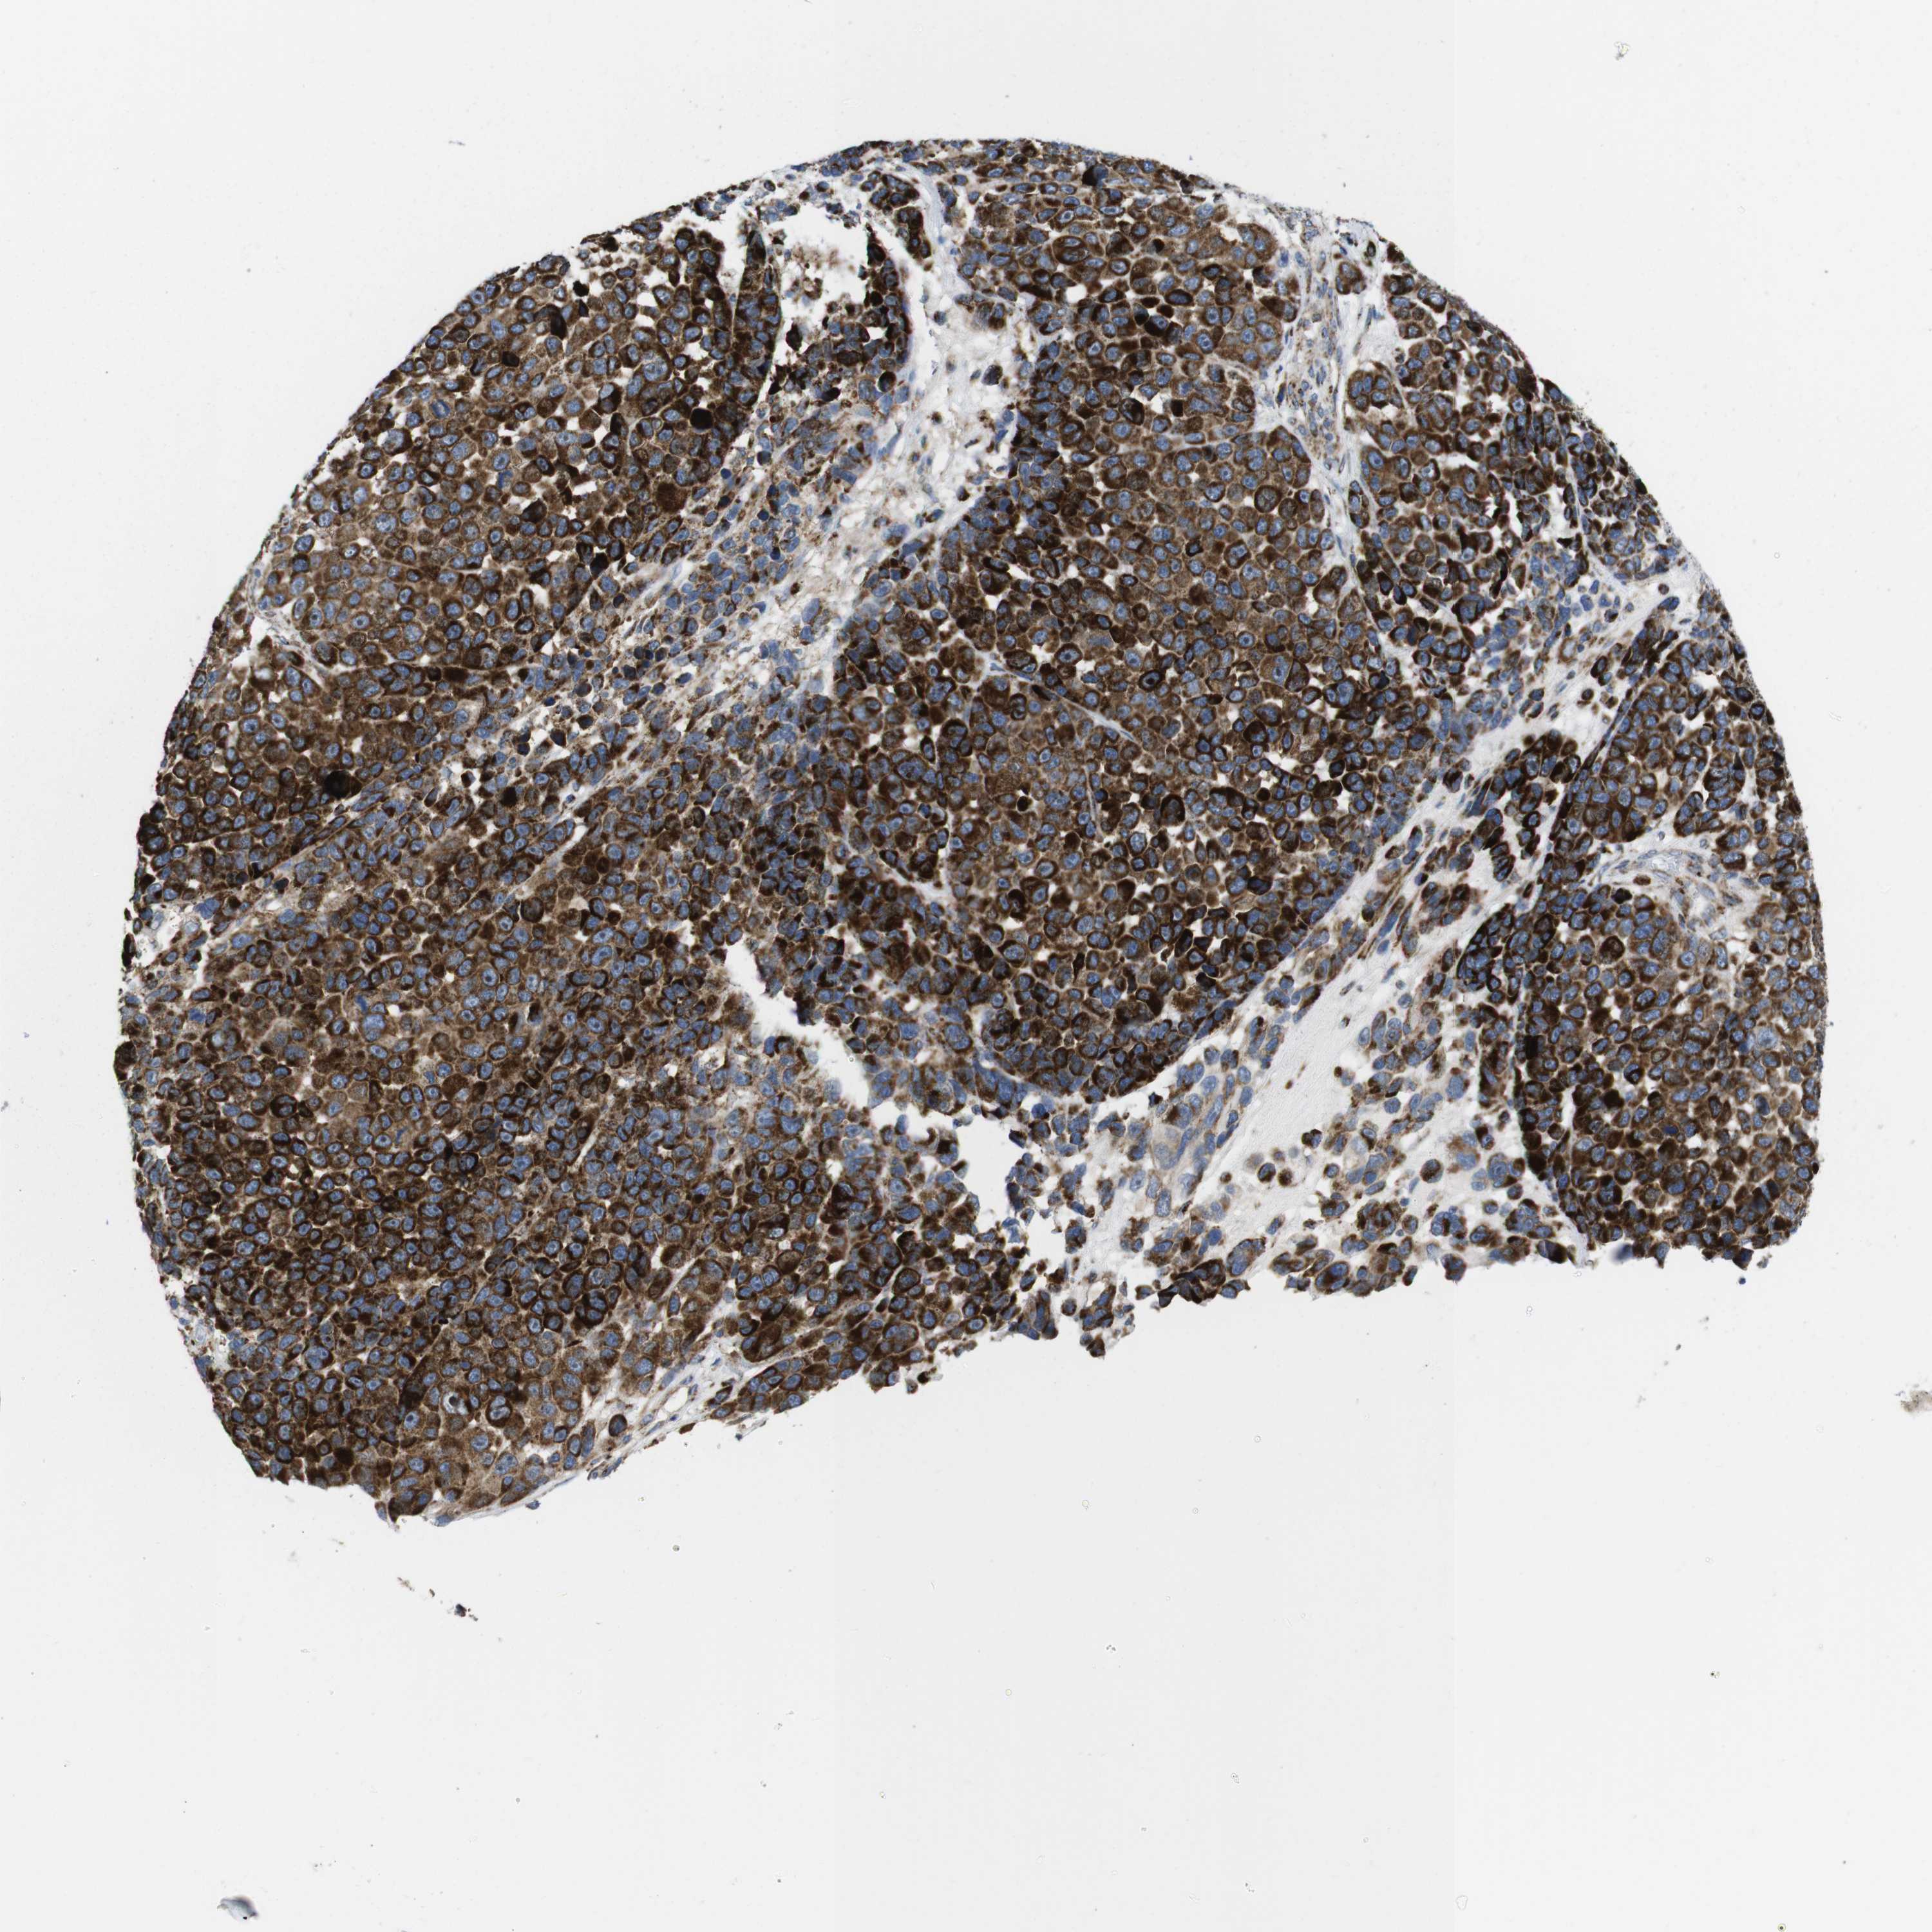

MELANOMA - Protein expressioni

A mouse-over function shows sample information and annotation data. Click on an image to view it in a full screen mode. Samples can be filtered based on level of antibody staining by selecting one or several of the following categories: high, medium, low and not detected. The assay and annotation is described here.

Note that samples used for immunohistochemistry by the Human Protein Atlas do not correspond to samples in the TCGA dataset.

Antibody stainingi

Antibody staining in the annotated cell types in the current human tissue is reported as not detected, low, medium, or high, based on conventional immunohistochemistry profiling in selected tissues. This score is based on the combination of the staining intensity and fraction of stained cells.

Each image is clickable and will lead to virtual microscopy that enables deeper exploration of all samples and also displays staining intensity scores, fraction scores and subcellular localization as well as patient and tissue information for each sample.

Antibody HPA014717

Antibody HPA024110

Staining

High

Medium

Low

Not detected

Intensity

Strong

Moderate

Weak

Negative

Quantity

>75%

75%-25%

<25%

None

Location

Nuclear

Cytoplasmic/membranous

Cytoplasmic/membranous,nuclear

Malignant melanoma, NOS

Malignant melanoma, Metastatic site